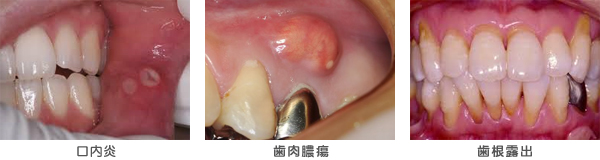

口内炎、膿瘍切開、歯肉や小帯の切除など、軟組織の治療に多く用います。また、歯根露出による知覚過敏症にも応用できます。

口内炎、膿瘍切開、歯肉や小帯の切除など、軟組織の治療に多く用います。また、歯根露出による知覚過敏症にも応用できます。

水分に吸収される性質があるので、組織の深部まで到達しにくく、安全な処置が可能です。また、組織に与えるダメージも電気メス等に比べ約1/2に抑えられるので治療も比較的早いのが特徴です。